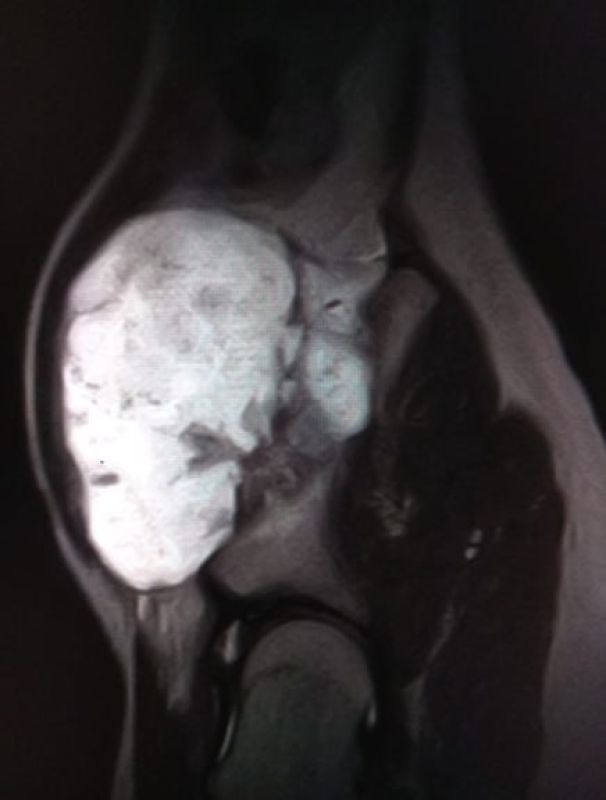

Подросток наблюдался с редким диагнозом — «экзостозная хондродисплазия». Это заболевание, при котором на кости образуется костно-хрящевое разрастание. У пациента оно достигло внушительных размеров, вызывало боль и причиняло дискомфорт. Также была угроза здоровью тазобедренного сустава.

У пациента нарост появился на тазовой кости, в сложной анатомической области. От хирургов требовалась особенная точность. Бригада врачей бережно удалила нарост, не задев сосуды и зоны роста. Недуг, который беспокоил мальчика, полностью ликвидировали.